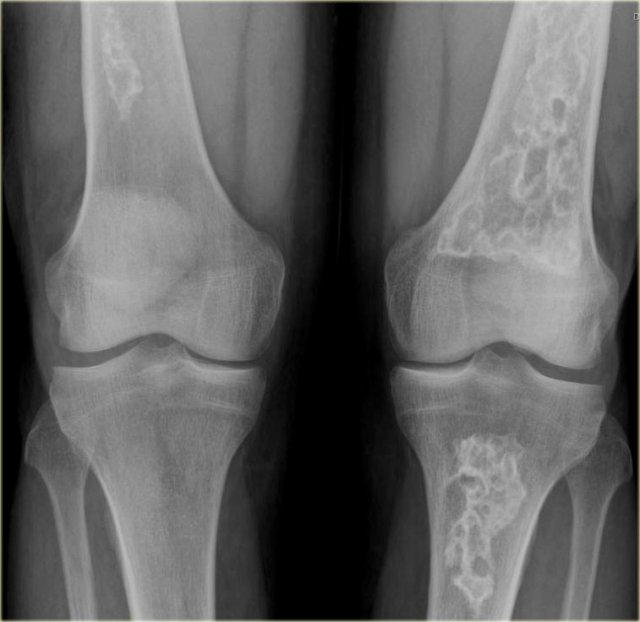

Phim X-quang cho thấy hình ảnh nhồi máu xương điển hình ở thân xương và hành xương của xương đùi và xương chày.

Trên hình ảnh MRI, nhồi máu xương được đặc trưng bởi các bờ không đều dạng rắn bò với tín hiệu thấp trên cả T1 và T2 WI, và tín hiệu mỡ từ trung bình đến cao ở phần trung tâm.

Tăng tín hiệu sau tiêm Gadolinium tĩnh mạch thường tối thiểu hoặc không có (xem hình bên phải).

Ở ngoại vi của ổ nhồi máu có thể thấy một vùng có cường độ tín hiệu tương đối cao trên T2WI.

Việc phân biệt nhồi máu xương với u sụn xương (enchondroma) hoặc u sụn xương ác tính độ thấp (low-grade chondrosarcoma) trên phim X-quang thường có thể rất khó khăn hoặc thậm chí không thể thực hiện được.

Các khối u sụn, đặc biệt là u sụn xương ác tính (chondrosarcoma), có thể biểu hiện hình ảnh xói mòn nội màng xương (endosteal scalloping), trong khi nhồi máu xương thì không có đặc điểm này.